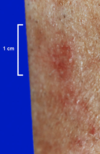

Contact Dermatitis

Pretibial Myxedema

(induration and thickening of the skin over the shins)

Actinic Keratosis